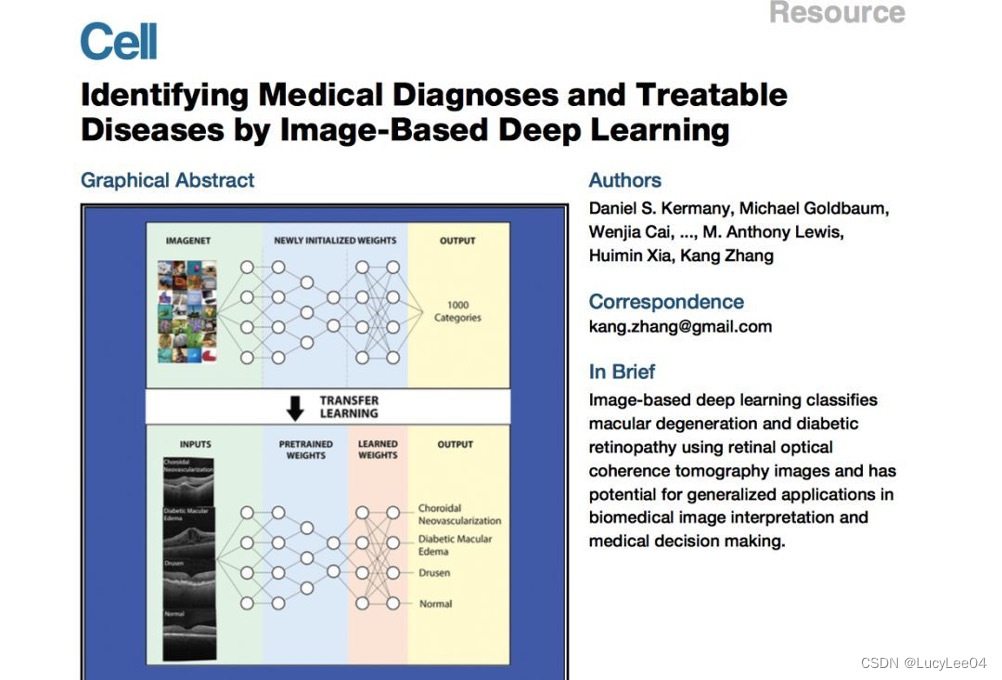

图像的分类->自动诊断